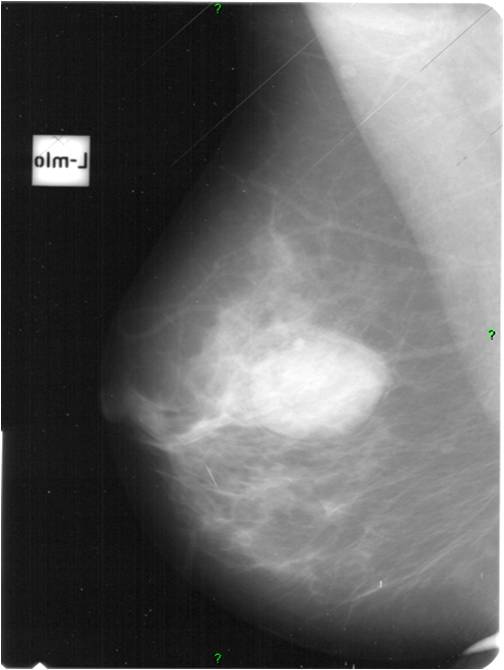

2. Digital mammography has displaced the analogue technic for today almost everywhere: (pictures 1,2,3) phosphorous plate or direct digital methods. For breast imaging the latter is the method of choice. Phases of image production separate. The image is produced on the detectors, but appears on the high resolution monitor and can be stored as a digital data set at various storage mediums (e.g.: CD, hard disk drives).

Image

Picture 1.

Picture 2.